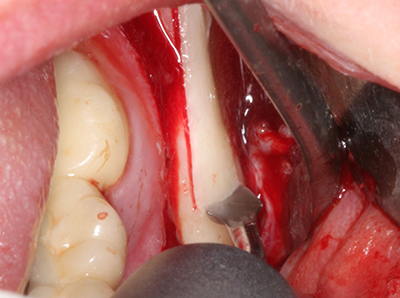

Piezosurgery has additional advantages when harvesting bone blocks. In addition to the high precision with osteotomy described above, the use of the thin saw tips specifically minimizes loss of material. Greater loss of material during harvesting can be expected with the thicker instrument tips, particularly when using Lindemann drills (Lakshmiganthan, Gokulanathan et al. 2012). The basal separation, which is necessary particularly for retromolar block transplants, is simplified by specially designed rectangular saws, with the result that piezosurgery is viewed as a precise, simple and safe procedure for harvesting retromolar bone blocks (Happe 2007) (Fig. 1-12).